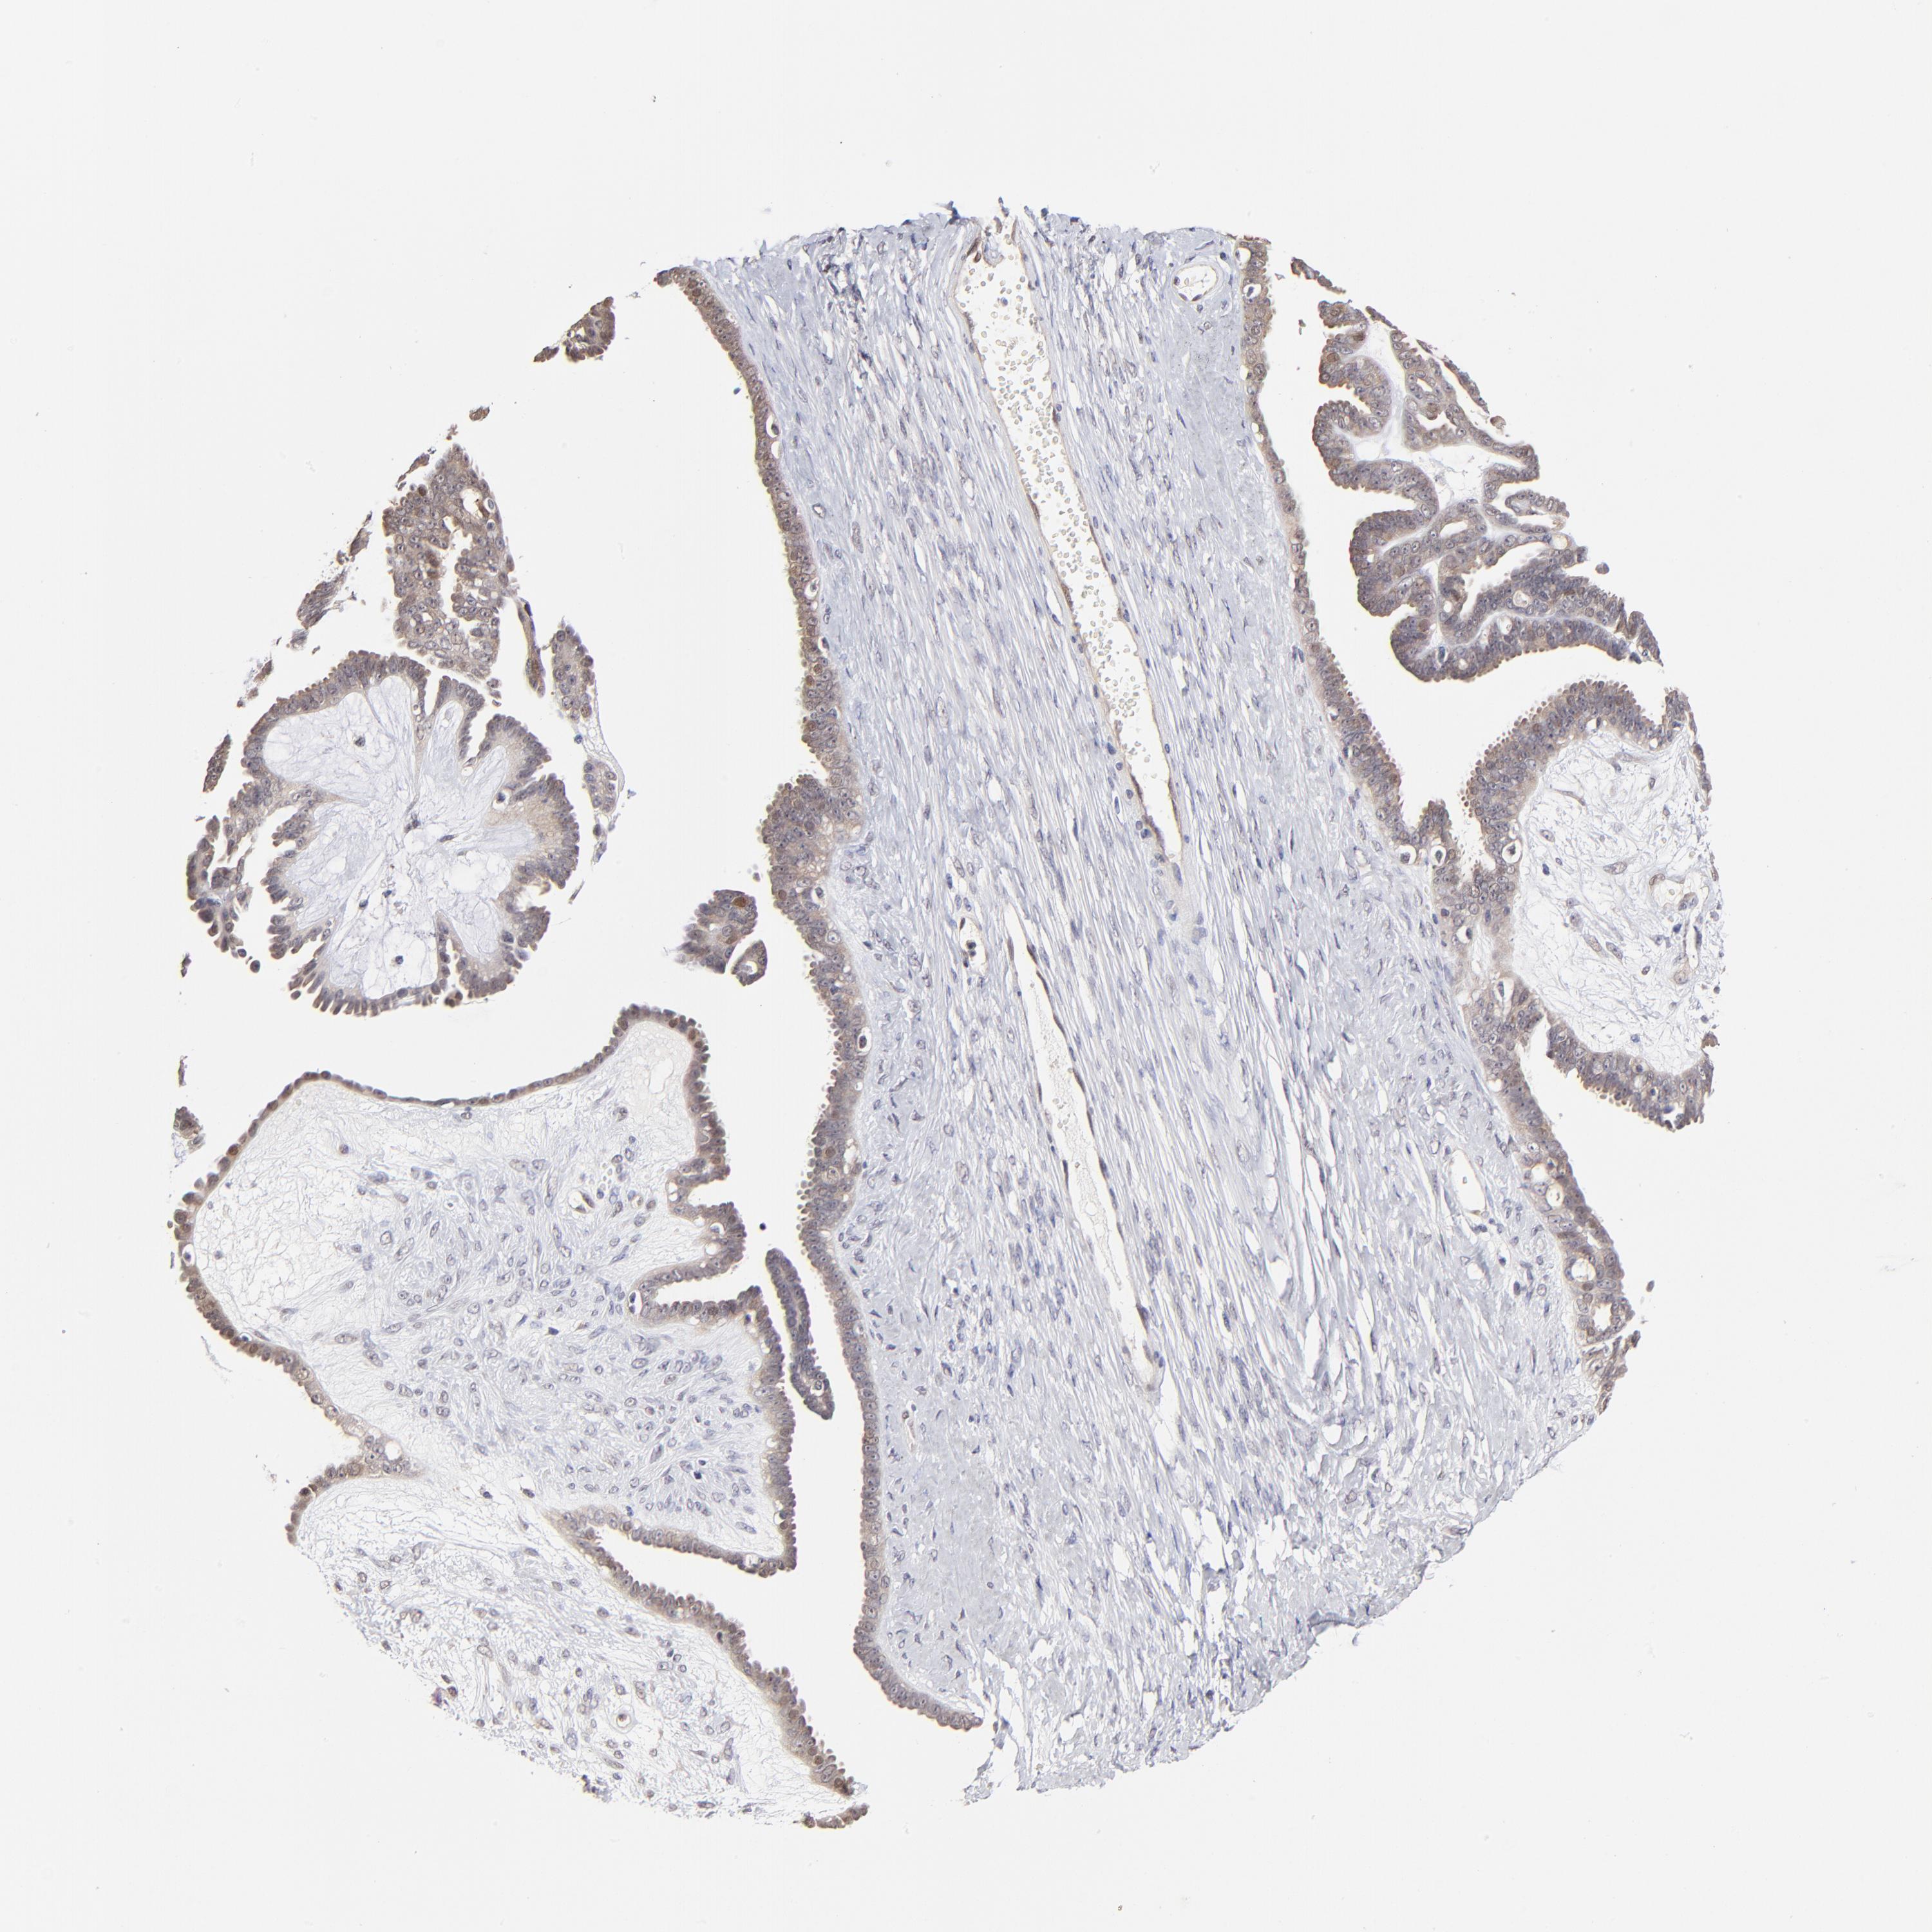

OVARIAN CANCER - Protein expressioni

A mouse-over function shows sample information and annotation data. Click on an image to view it in a full screen mode. Samples can be filtered based on level of antibody staining by selecting one or several of the following categories: high, medium, low and not detected. The assay and annotation is described here.

Note that samples used for immunohistochemistry by the Human Protein Atlas do not correspond to samples in the TCGA dataset.

Antibody stainingi

Antibody staining in the annotated cell types in the current human tissue is reported as not detected, low, medium, or high, based on conventional immunohistochemistry profiling in selected tissues. This score is based on the combination of the staining intensity and fraction of stained cells.

Each image is clickable and will lead to virtual microscopy that enables deeper exploration of all samples and also displays staining intensity scores, fraction scores and subcellular localization as well as patient and tissue information for each sample.

Antibody HPA003204

Staining

High

Medium

Low

Not detected

Intensity

Strong

Moderate

Weak

Negative

Quantity

>75%

75%-25%

<25%

None

Location

Nuclear

Cytoplasmic/membranous

Cytoplasmic/membranous,nuclear

Carcinoma, endometroid

Cystadenocarcinoma, serous, NOS